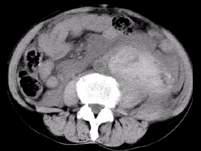

问题 男,37岁,左腰部疼痛伴血尿,有外伤史,CT检查如图所示,下列说法错误的是 ( )

选项 A、考虑为肾挫伤 B、考虑为肾包膜下出血 C、左侧肾实质增厚,其内密度不均,可见大片状不规则的高密度影 D、腹腔内可见较高密度的积液 E、左侧肾影增大模糊,肾轮廓消失

答案 B